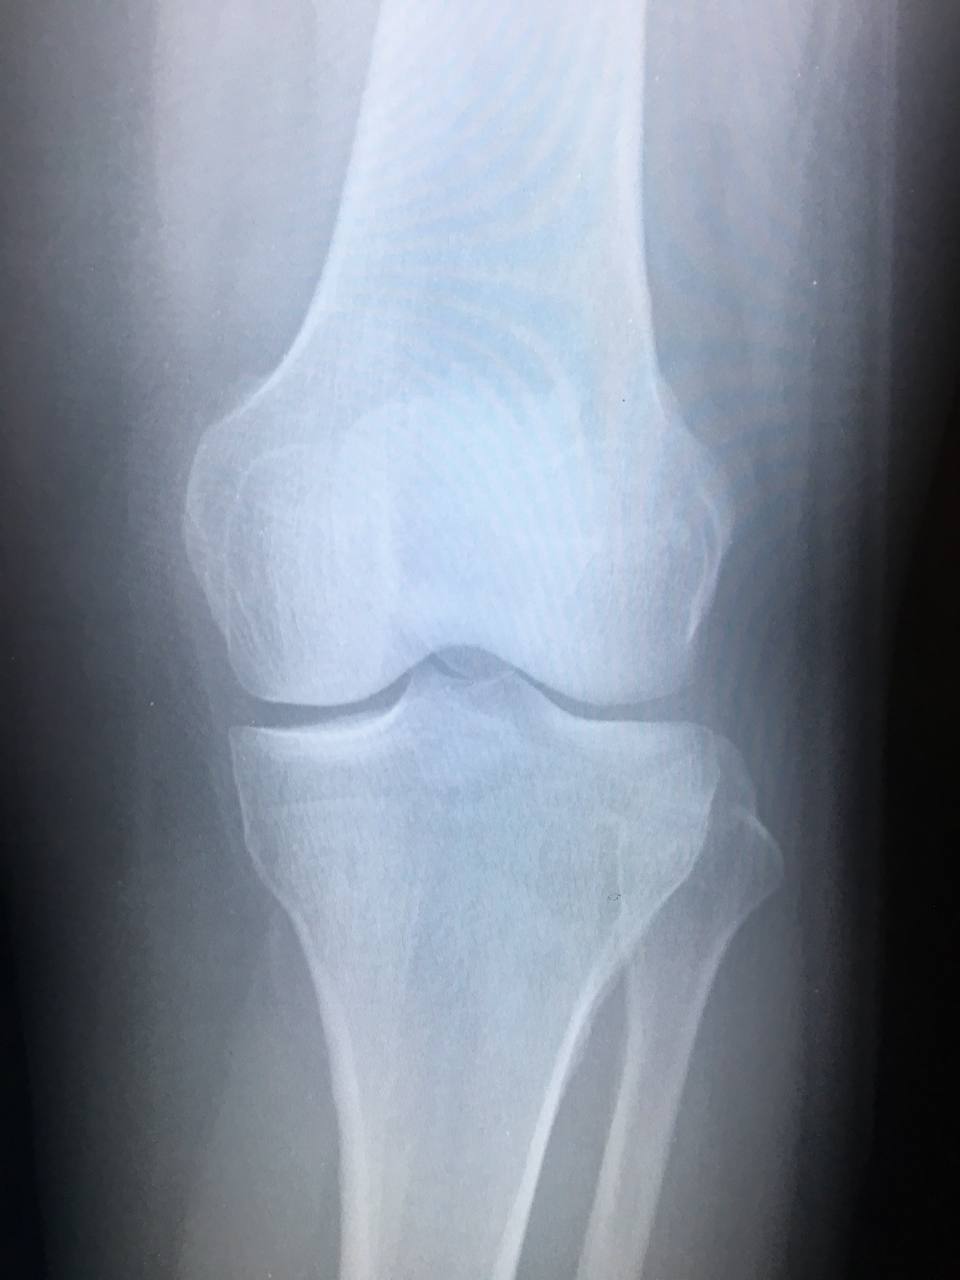

Добрый день вечер. Жалобы на боль в к/суставе. Отек. Кальцинат/добавочная косточка?

Норма